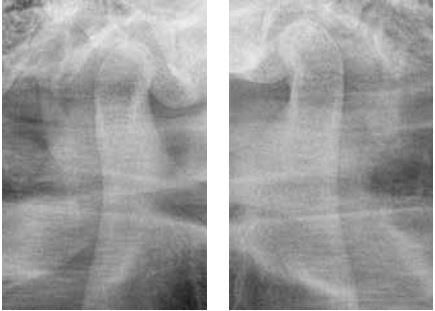

Đánh giá vị trí hàm dưới bằng X-quang khớp thái dương hàm (TMJ) hoặc CBCT

Để đánh giá vị trí của lồi cầu trong hố khớp thái dương hàm, độ ổn định của vị trí hàm dưới cũng như phát hiện các vùng thấu quang gợi ý tình trạng viêm, sự dẹt của lồi cầu hoặc hình thành gai xương (osteophyte) thì chụp X-quang khớp thái dương hàm hoặc CT chùm tia hình nón là những phương tiện hữu ích.

Dựa trên kết quả của lần thăm khám ban đầu này, chúng ta có thể dự đoán liệu có thể đạt được hiệu quả hít dính tốt ở hàm dưới hay không, hoặc liệu có cần thiết kế một loại hàm giả điều trị đặc biệt hay không.